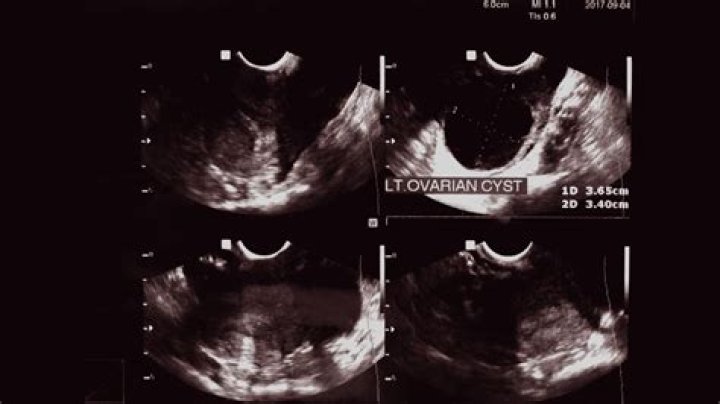

How do you detect ovarian cysts?

Ovarian cysts

1. Physical exam. A doctor may feel a cyst during a pelvic exam.

2. Ultrasound. An ultrasound can pinpoint the location, size, and makeup of ovarian cysts. ...

3. Blood tests. If you are past menopause or at increased risk for ovarian cancer, your doctor may order CA-125 testing along with other diagnostic studies.